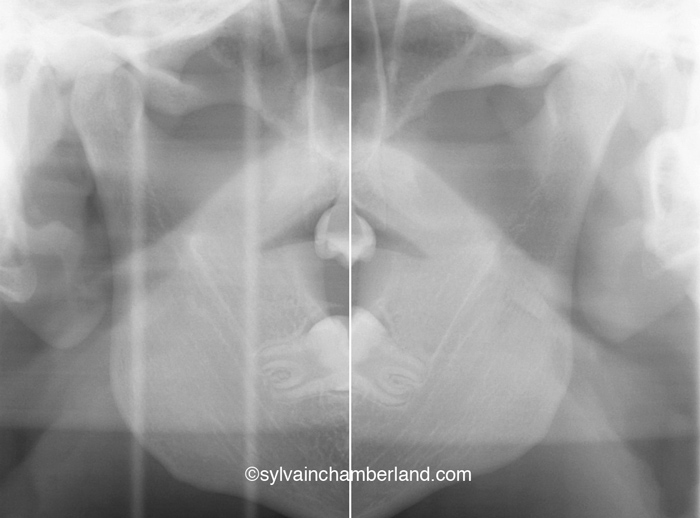

Condyle normaux et béance antérieure

La photo à gauche représente une béance antérieure.

La radiographie à droite montre des condyles de formes normales.

Dans ce cas-ci la béance s’explique par un excès vertical du maxillaire. Observez, sur la radiographie céphalométrique de gauche, la grande distance entre les racines des dents postérieures supérieures et le palais. C’est l’indication d’un excès vertical. La longueur de la branche montante est normale et l’angle goniaque est à la hauteur de la 2e vertèbre cervicale.

Ces deux cas illustrent une malocclusion avec béance antérieure, mais deux étiologies totalement différentes. Dans le 1er cas, la béance antérieure s’explique par la résorption condylienne. Dans le 2e cas, la béance s’explique par un excès vertical du maxillaire supérieur.

Le 2e cas a subi une chirurgie orthognathique bimaxillaire conventionnelle avec repositionnement supérieur du maxillaire, ostéotomie mandibulaire et génioplastie.